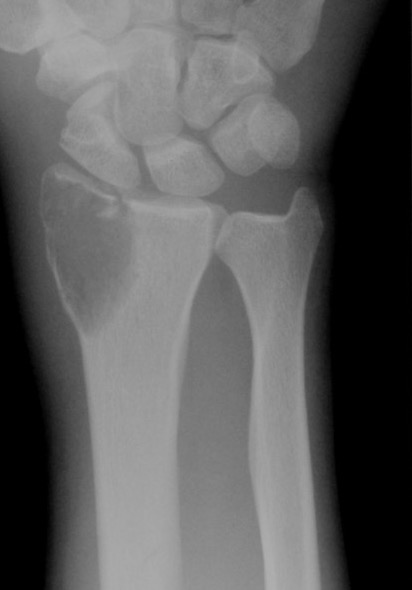

X-ray

Eccentric, sharply demarcated lytic lesion

- no sclerosis around lesion

- narrow zone of transition

- metaphysis, extending into epiphysis

- no mineralization